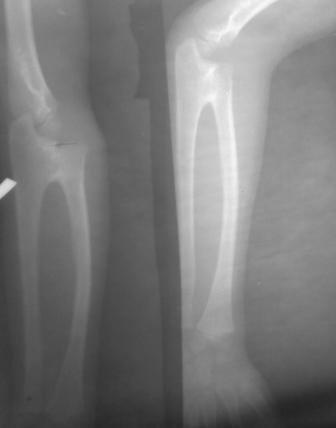

Врожденный синостоз лучевой и локтевой кости

Уважаемые коллеги. Обратился мальчик 10 лет, с врожденным синостозом в проксимальном эпиметафизе лучевой и локтевой кости,

сгибание и разгибание в полном объеме, кисть в положении пронации, супинация отсутствует, из-за чего нарушена многие функции кисти. Больной и родители просят по возможности восстановить функции кисти-супинацию!

Уважаемый Абдурашид. Не совсем обычная рентгенологическая картина для врожденного синостоза проксимального радиоульнарного сочленения. Отсутствие (рентгенологически) выраженной дугообразной деформации диафиза лучевой кости заставляет думать о минимальной выраженности пронационной контрактуры предплечья.